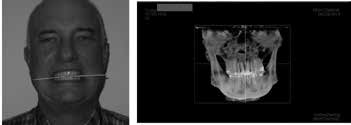

There were no positive findings for muscle, tendon and ligament palpation. Imaging utilizing CBCT (cone beam computed tomography) demonstrated a significant cant of the mandible to the left side (affected side) and was confirmed with photograph of patient with tongue blade, see Figures 6 and 7. This indicates that the elevator muscles or muscles of mastication are shorter on the left than right. When muscles are shorter than their resting length they have greater resting tonus or tension.